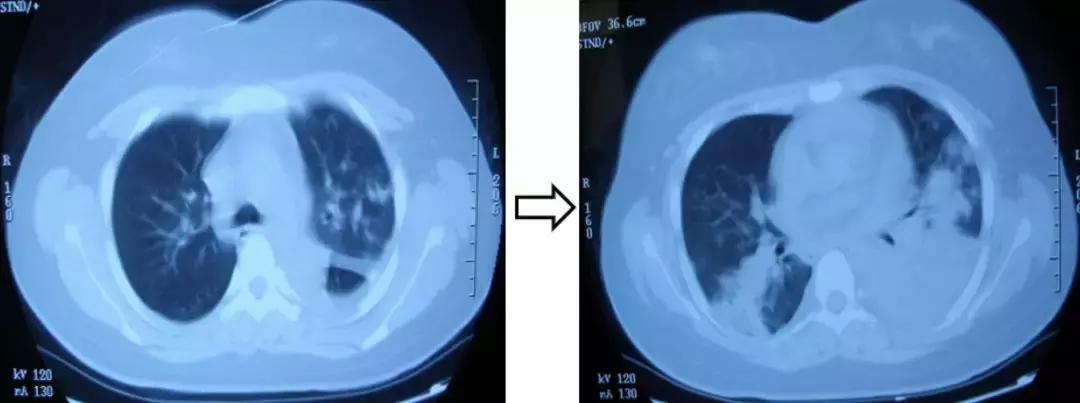

先来看看这张胸部CT :

这是一个20岁的女性,高热、咳嗽伴呼吸困难1周,血气分析:Ⅰ型呼吸衰竭,血常规:正常。可以看到影像学是在进展的。

那么是不是肺部感染(CAP)?很难诊断,于是做了肺穿刺。两次肺穿刺活检为慢性炎症改变,应用皮质激素治疗,症状缓解,复查病灶基本吸收。最后诊断为肺血管炎病变。